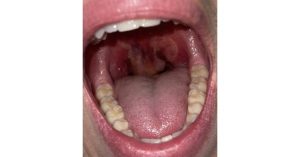

uvulitis nov 2024 featured